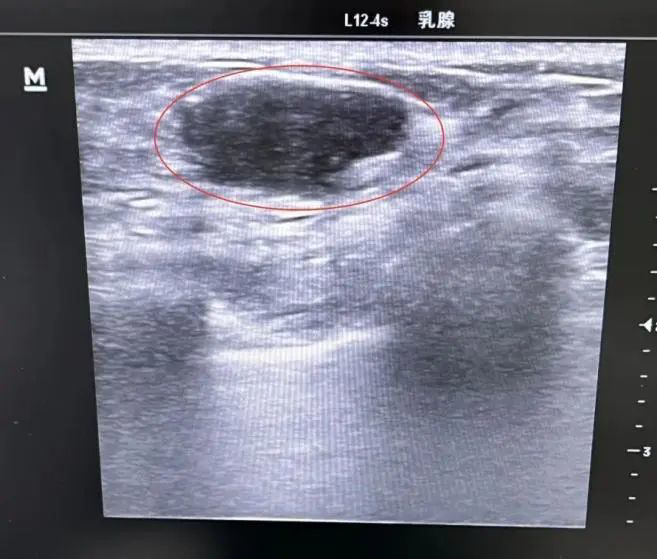

B超下的乳腺结节